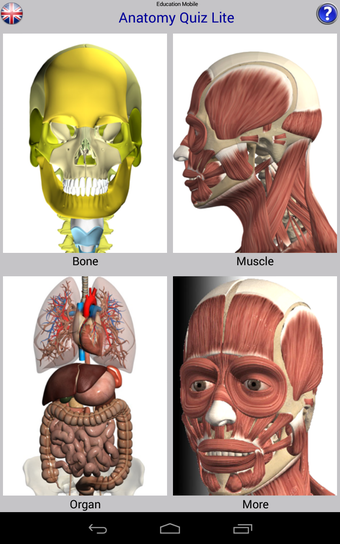

Anatomía Quiz Gratis: Una aplicación completa para aprender anatomía humana.

Anatomy Quiz Free es una aplicación de Android de Education Mobile que ofrece una amplia gama de cuestionarios para ayudar a los usuarios a aprender anatomía humana. La aplicación cuenta con más de 500 cuestionarios que ponen a prueba tu capacidad para identificar la ubicación correcta de un objeto dado su nombre. Los cuestionarios se generan a partir de modelos de anatomía 3D virtuales, lo que los hace más atractivos e interactivos. La aplicación es gratuita y no hay versiones premium ni compras dentro de la aplicación.